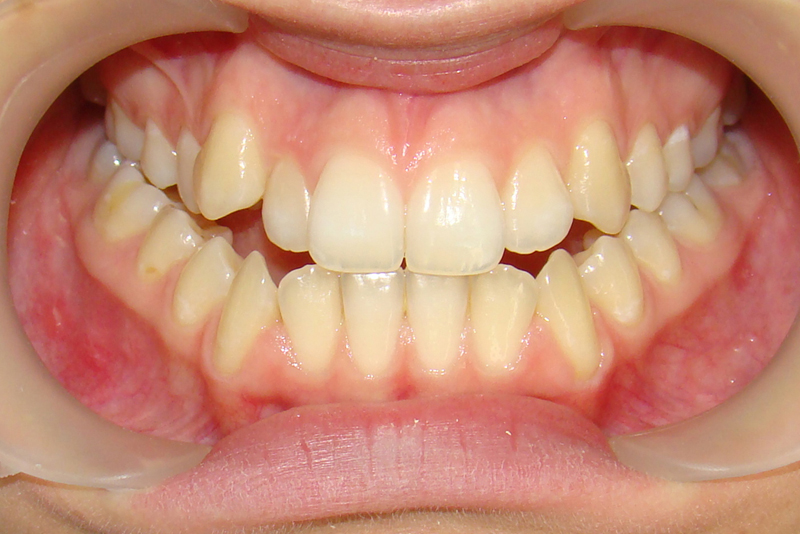

Девушке 14 лет. Получилось все исправить без удаления зубов

А это уже молодой человек 10 лет. Тоже получилось справиться без удаления. Хоть оно и было показано. Но мальчик очень упорно носил специальные аппаратики и резиночки. Покажу со всех сторон. Этот случай победил в конкурсе на конференции